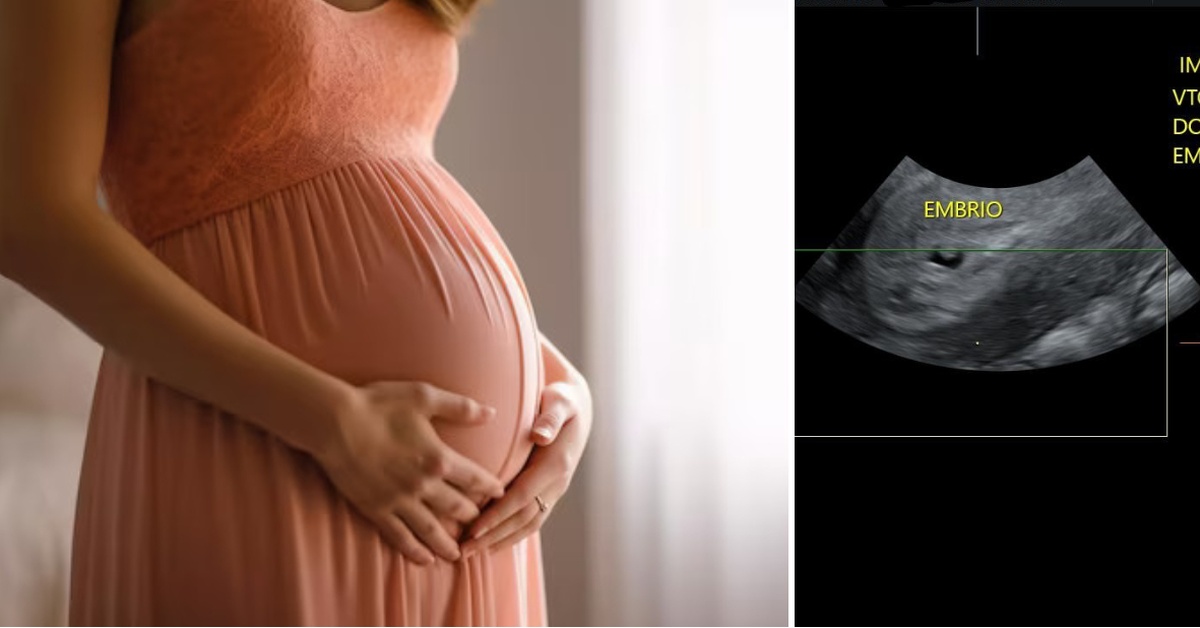

Најголемата среќа: По долга борба за бебе, 44-годишна жена забремени со инвитро во болница „Плодност“

По долга борба за бебенце, жена успеа да забремени на 44-годишна возраст со инвитро направено со помош на врвните специјалисти од реномираната болница за гинекологија и акушерство.

Ова е второ инвитро на парот кој е во брак 20 години. Првото инвитро било направено на друго место.

„Пациентката има 44 години, во брак е 20 години. Станува збор за ниска оваријална резерва која изнесува 0,6, а нормалните вредности се во опсег 4-7,2. Ова ѝ е второ ИВФ, а првото беше направено на друго место. Применета ембриоскопија, која единствено од овој вид се прави кај нас, што резултираше со успех“ – стои во објавата од болницата.